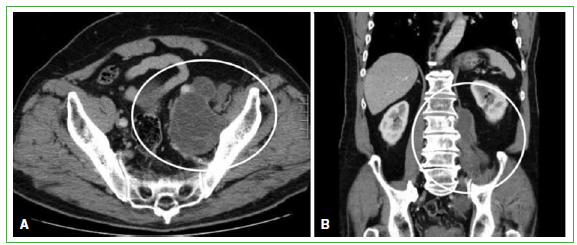

Figura 4.

Tomografía computarizada de abdomen y pelvis. A. Corte transversal. Se observa una lesión paravertebral derecha en relación con la articulación sacroilíaca. B. Corte coronal. Se visualiza una masa paravertebral de L4 a S1 derecha. (Agosto de 2009).